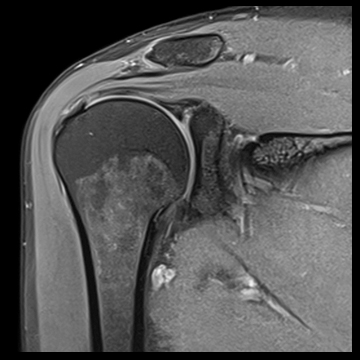

肩関節

T1 TSE FatSat,

T2 TSE FatSat,

T2 TSE,